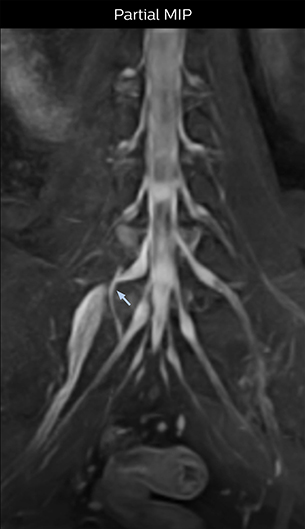

At Northern Fukushima Medical Center in Japan, excellent MRI visualization of nerves helps support confident diagnoses and informs surgical treatment decisions for patients with lower limb symptoms. MRI technologist Tanji and orthopedic surgeon Dr. Yabuki share how direct nerve visualization with the 3D NerveVIEW method adds information when diagnosing atypical herniations. The additional insights changed their way of working and benefit their patient care, as illustrated by some clinical examples.

“In patients with lower extremity neurological symptoms, NerveVIEW helps us to determine the disease matching the patient’s symptoms by directly visualizing the nerves. We use the sequence mainly, when there is suspicion of intraforaminal stenosis, extraforaminal stenosis or lateral disc herniation, which is often based on routine T2- and T1-weighted images. Additionally, the excellent depiction of the course of nerves makes NerveVIEW a good navigator when applying treatment such as block therapy or surgery.”

“In such case, we would then browse through axial T2-weighted MR images slice by slice and mentally reconstruct the actual situation based on both radiculography and MRI. Fortunately, NerveVIEW can now very well show nerve courses and presence of nerve compression or edema in one single image series.” “We have often seen NerveVIEW directly depict details of the nerve compression that were not observed by radiculography. Therefore, we think that with NerveVIEW we can reduce the number of invasive examinations, especially for some patients with lumbar plexus symptoms.”

“The intra-luminal signal of veins, especially around the intervertebral space, can be suppressed well with NerveVIEW. As a result, we can easily observe the detailed nerve structure around the posterior ganglion,” he says. “This is why we use 3D NerveVIEW for intraforaminal stenosis and extraforaminal stenosis/herniation (lateral disc herniation). On the other hand, if herniation is suspected to exist inside the dorsal root ganglion (DRG), balanced TFE or ProSet-FFE is applied. NerveVIEW is not suitable for evaluating the median type of herniation.” The SE-EPI DWI-based method for MR neurography works well for large FOV exams like whole-body MRI, but focal examination of nerves is often limited by the attainable spatial resolution (both inplane and slice direction) and geometric distortion. “3D NerveVIEW achieves higher in-plane resolution – close to our other routine spine sequences – and the source images can be used instead of adding a fat-suppressed T2-weighted sequence,” Tanji says.

According to Tanji, methods such as ProSet FFE, STIR or 3D VISTA are anatomically nonselective because background signals, for instance from blood vessels, often interfere with nerves, which hampers evaluation of details, especially at the peripheral side of the nerves.

“Recently, the two surgical methods extreme and oblique lateral interbody fusion (XLIF and OLIF) have become mainstream for minimally invasive treatment of lumbar spinal canal stenosis and intervertebral foramen stenosis. With these surgical techniques, the spine is approached from the flank, and prior knowledge of the exact anatomy of the lumbosacral plexus would be extremely helpful. To that end, high slice resolution (less than 1 mm acquisition) that enables sharper sagittal MPR images will be needed.”

“For both brachial and lumbar plexus, we are currently using a 230 mm FOV and voxels of about 1 x 1 x 2 mm acquired (1 x 1 x 1 mm reconstructed). This provides us a good representation of the nerves, even though this FOV is relatively small. Regarding the inplane resolution, we hope to be able to bring that down to 0.7 mm, similar to our typical 2D multislice T2W images,” says Tanji.